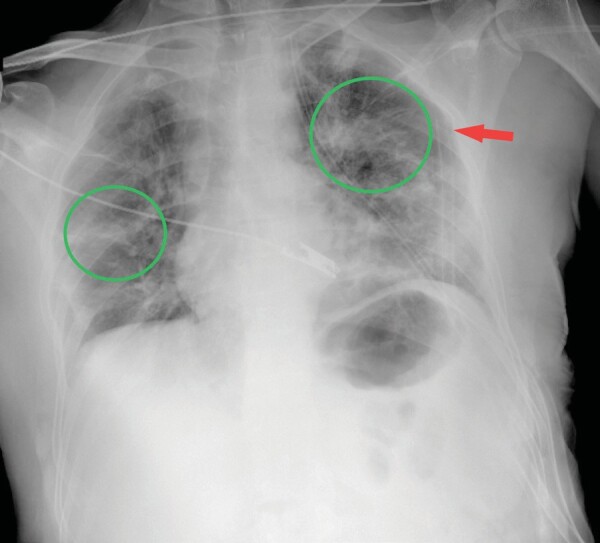

Birt-Hogg-Dubé syndrome: A case series highlighting pulmonary manifestations, rare renal involvement and role of familial diagnosis.